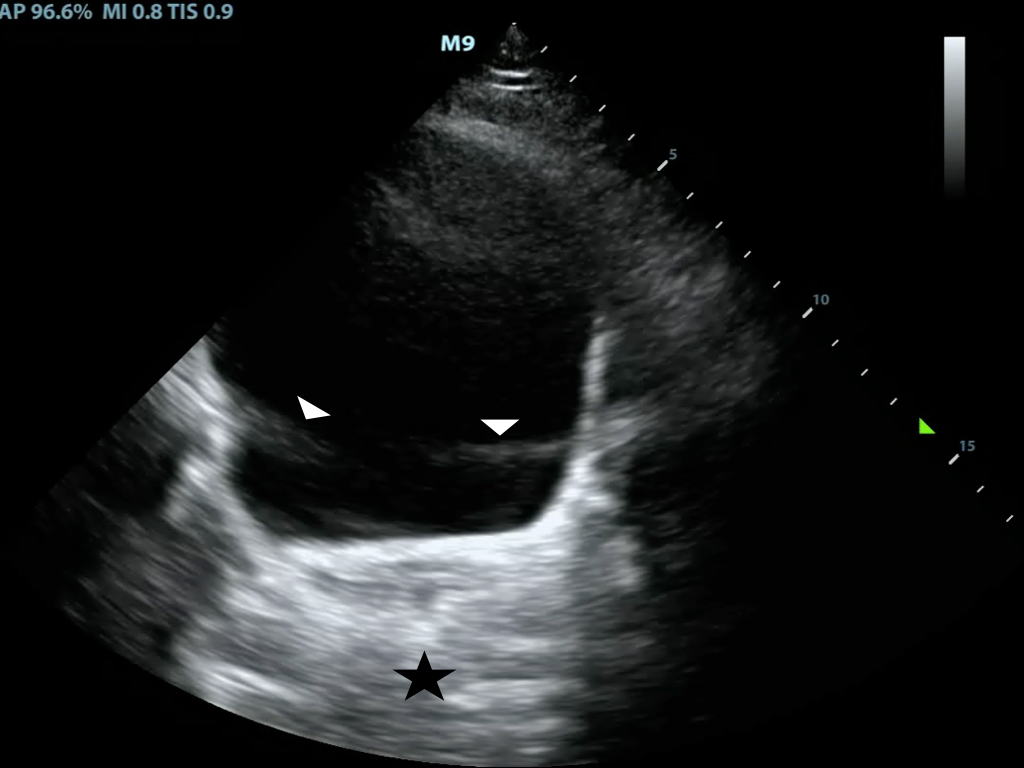

- Spectral Doppler consists of a continuous and pulsed-wave form

- Pulsed-wave spectral Doppler

- Transducer sends pulses of ultrasounds to a predetermined depth

- Transducer then listens for returning echoes to determine flow velocities at that given location

- The “spectrum” of the returned Doppler frequencies are plotted in a characteristic two-dimensional display (Figure 5)

- Venous flow demonstrates a more continuous, band like shape

- Arterial flow shows a more triangular shape1-8

- Figure 5. Pulse wave doppler of flow through the mitral valve